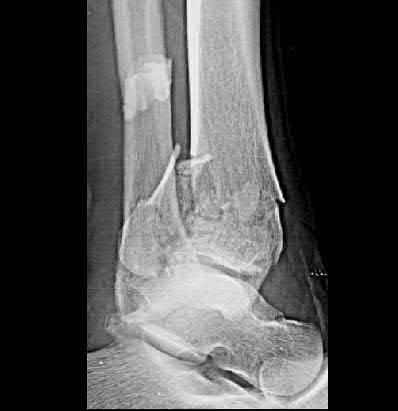

A 55-year-old female presents to the emergency room after falling off her balcony. She sustained the isolated, closed injury shown in Figures A and B. She is otherwise healthy, but routinely smokes 30 cigarettes per day. What would be the most appropriate sequence of treatment steps for definitive management of this injury?

Figures A and B show radiographs of a comminuted AO/OTA C3 fracture of the distal tibia. The most appropriate steps in the management of this patients injury would include: Closed reduction and splinting, external fixation, CT scan, and delayed open reduction internal fixation in this sequence.

Infection and wound healing problems are common with comminuted distal tibia fractures due to an increased incidence of soft-tissue complications associated with the operative management. Patients with a history of diabetes and smoking are at further risk. To decrease the risk of complications in this patient, a two-staged, delayed open reduction internal fixation technique is the best option for the treatment of severe pilon fractures.

Patterson et al. reviewed 23 consecutive patients with comminuted distal tibia fractures. They showed 0% infections or wound-healing problems in their patient population treated with a two-staged protocol. Their protocol involved fibula fixation with an intramedullary implant and application of a medial external fixator to to regain length and restore anatomic alignment. Re-evaluation of the limb occurred ten to fourteen days later for definitive fixation.

Sirkin et al. retrospectively reviewed 40 closed and 82 open pilon fractures (AO types 43A-C) that were treated with staged surgical management (avg. time from ext. fix. to formal reconstruction was 14 days (range 4 to 31) They reported 17% post-operative wound complication in the closed group and 11% post-operative wound complication in the open group (Gustilo Type I-III). They suggest the technique was successful in both closed and open pilon fractures.